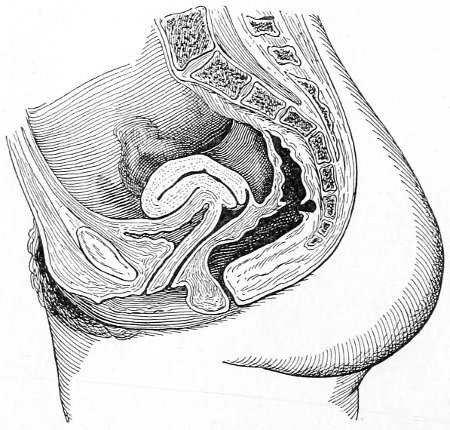

Fig. 2.—Bimanual examination.

In making the bimanual examination the structures 25 should be palpated methodically in order. The vaginal finger notes the condition of the cervix uteri. If the fundus be in the normal position, the uterus can then be taken between the abdominal hand (upon the fundus) and the vaginal finger (upon the cervix) (Fig. 3). The shape, size, mobility, and consistency are noted. The vaginal finger is then passed anteriorly and laterally toward either uterine cornu, while the abdominal fingers pass over to the posterior aspect of the same cornu. The ovarian ligament and the proximal end of the Fallopian tube may thus be felt. Passing farther outward, the whole of the tube and the ovary may be examined. The same procedure is then applied to the opposite side.

Fig. 3.—Bimanual examination; median sagittal section of the pelvis.